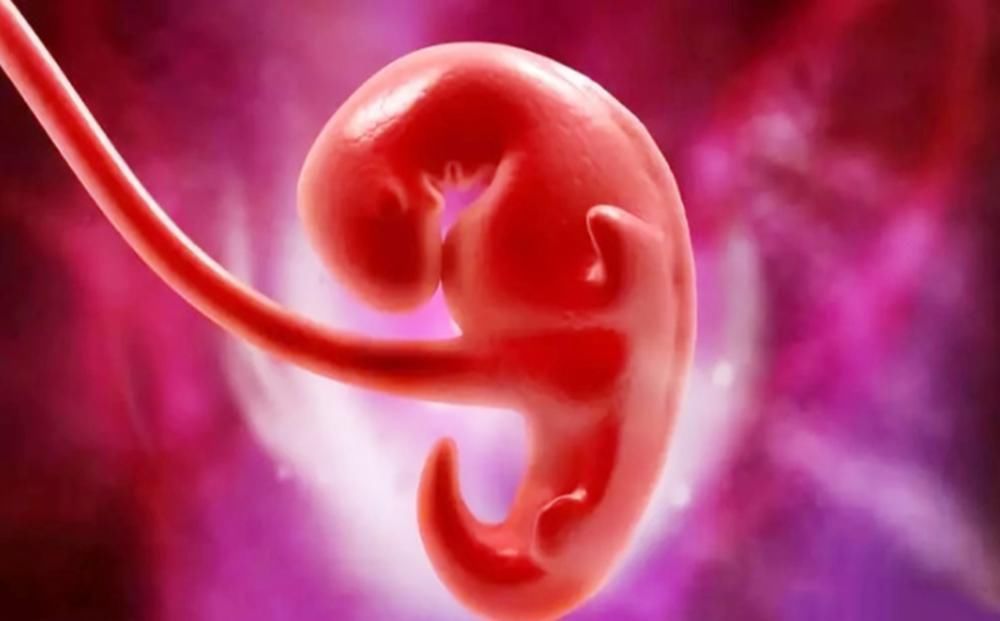

“胚胎”和“胎儿”如何划分?精子和卵子结合受精卵,受精卵再经过不断的分裂形成胚胎,这个过程(孕0-2周)就是从胚种期进入到胚胎期;

而胚胎期各个原始细胞又开始继续分化,逐渐形成各种器官,像大脑、心脏、四肢、眼睛、鼻子、嘴(孕3-8周)等;

等到怀孕第8周的时候,从B超上看就能清楚地看到发育的形态,甚至还会有胎动,这个时候就预示着正式从胚胎期进入到了胎儿时期(孕9-分娩)。